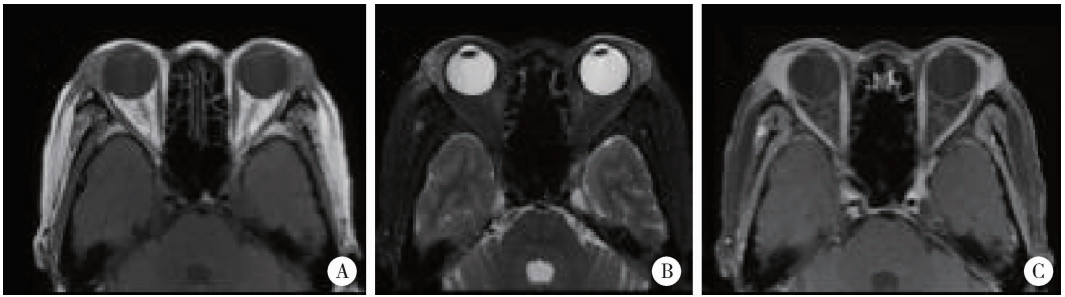

Figure 2

Orbital magnetic resonance imaging of lacrimal gland enlargement in sarcoidosis Orbital magnetic resonance imaging demonstrates bilateral lacrimal gland enlargement with anterior displacement, exhibiting mildly hypointense signal on T1-weighted imaging (A) and hyperintense signal on T2-weighted imaging (B), with marked enhancement post-contrast administration (C)."